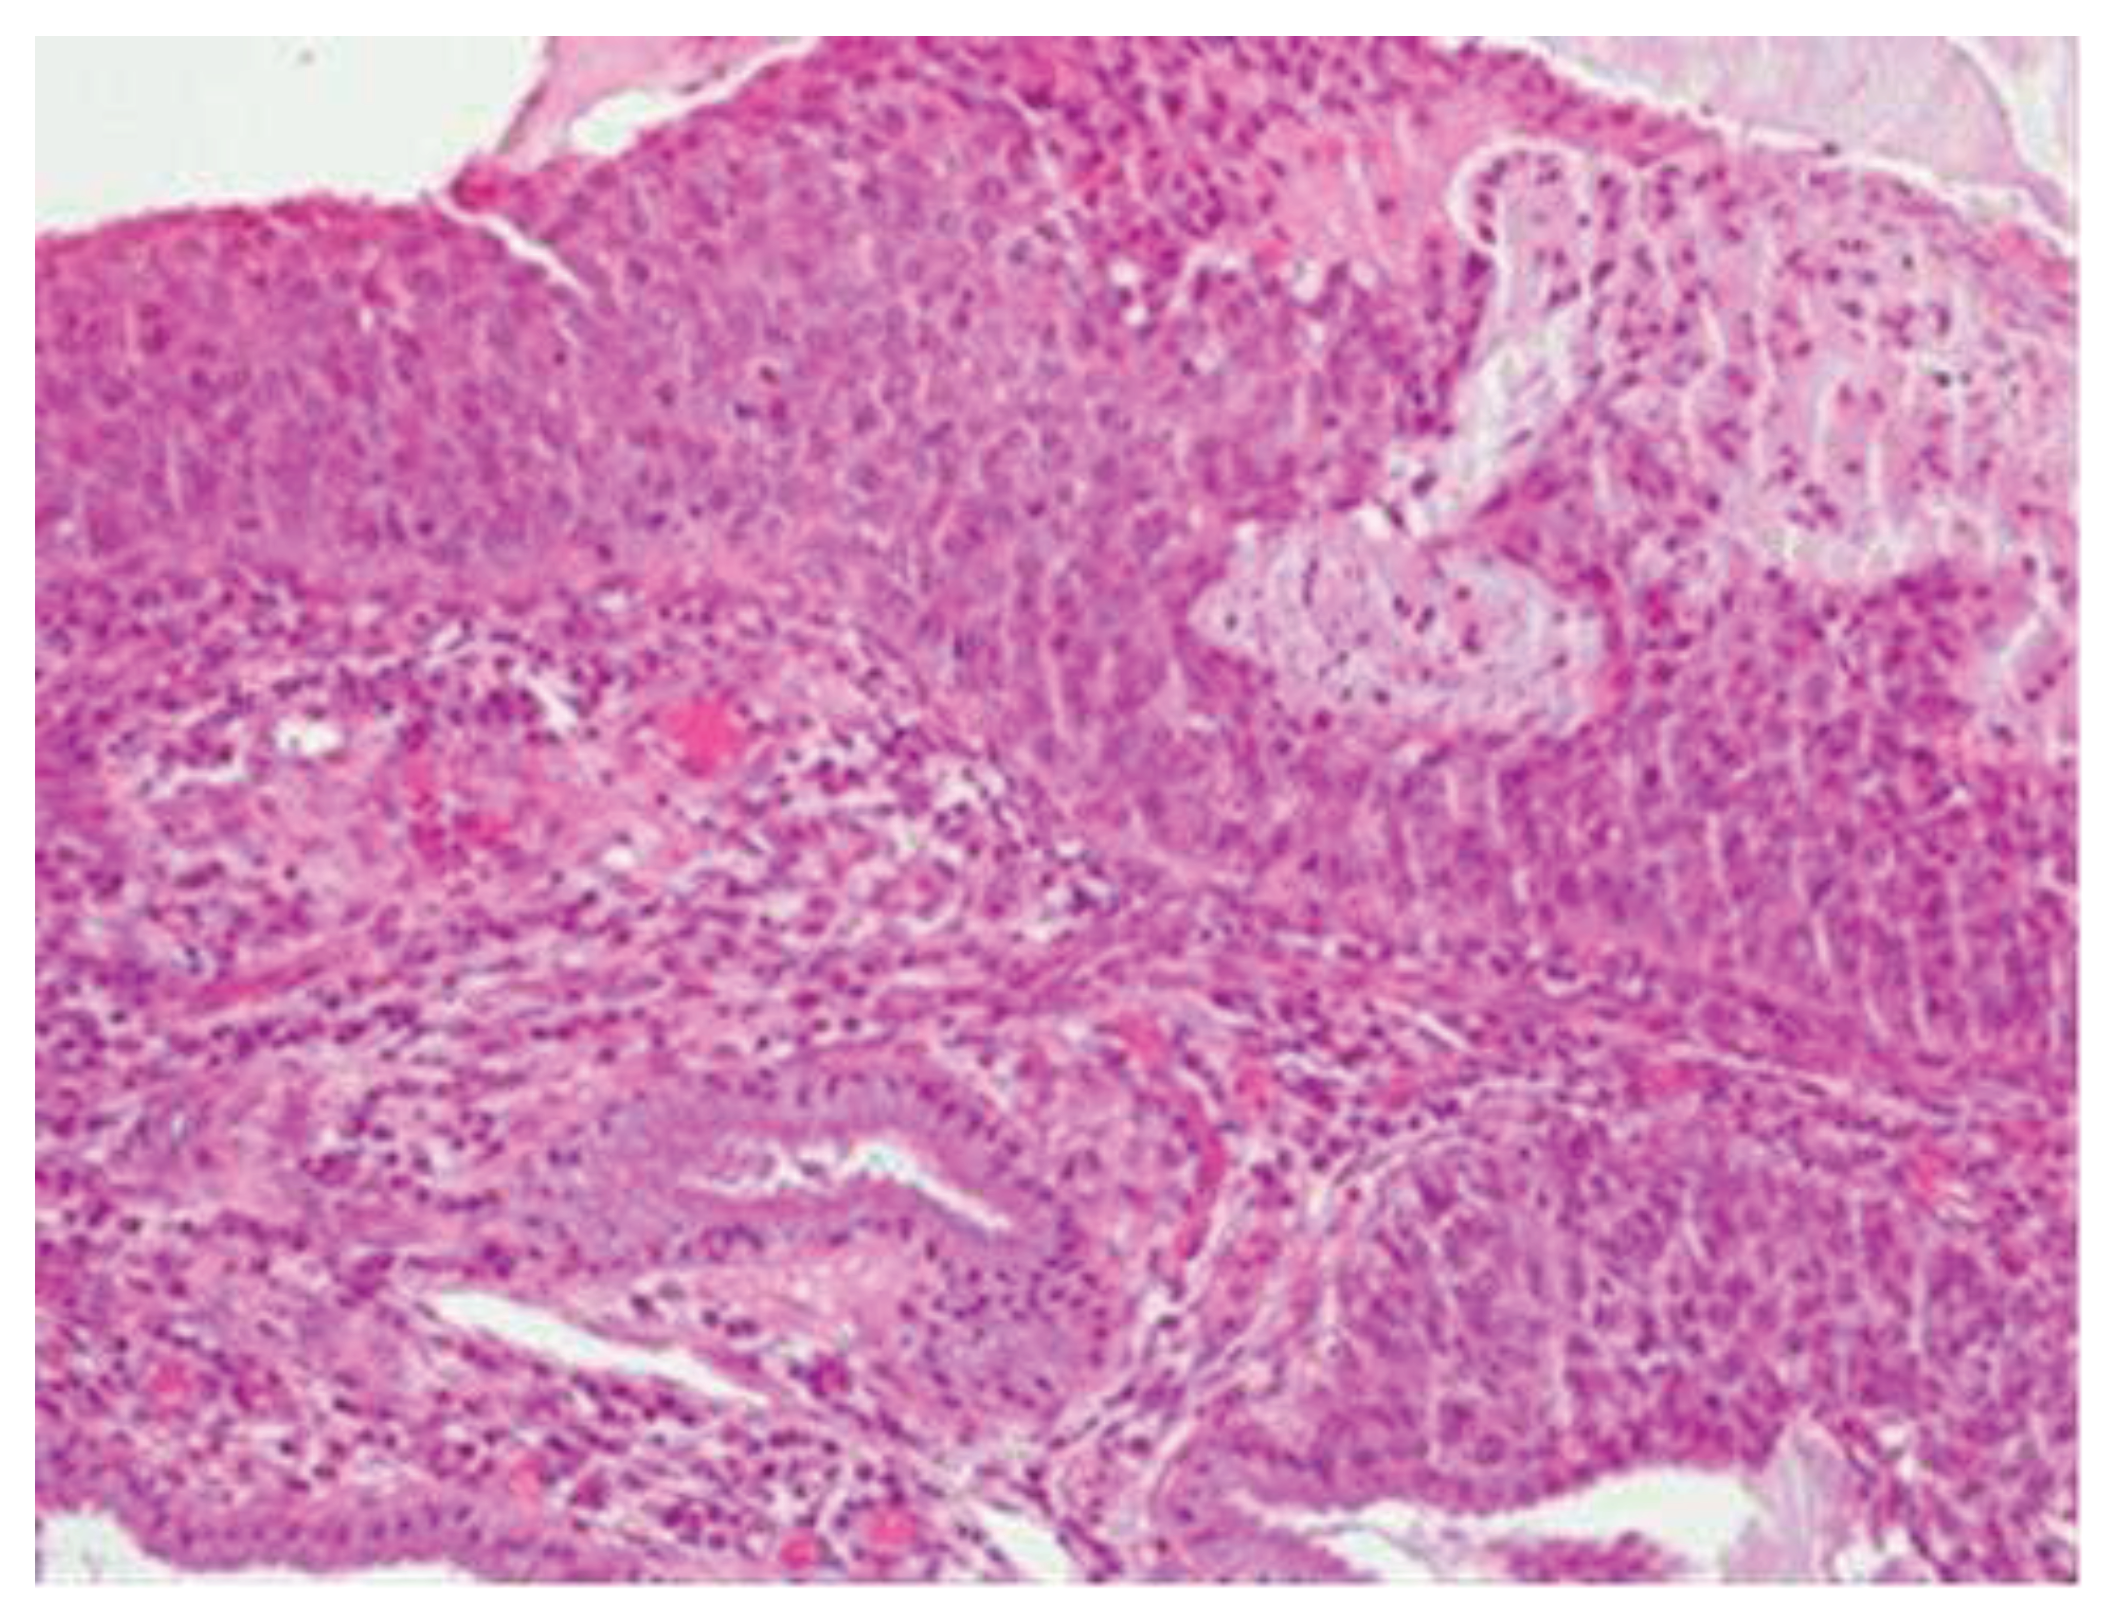

Morphologically, enlarged and hyperchromatic nuclei, clumped chromatin, irregularities, and notches in the nuclear membrane, and altered nuclear/cytoplasmic ratio can be observed. Mitotic figures at various levels are also frequent (Figure 3 and Figure 4).

Figure 3-4. CIN3 histological sample.